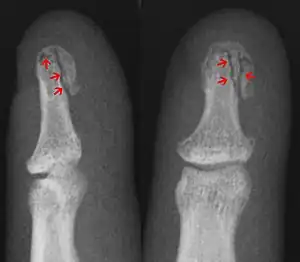

A mallet finger due to an avulsion fracture | |

Fractures in the joints are often caused by jammed finger injuries, the hand equivalent of a stubbed toe. If a tendon pulls away the bit of bone to which it is attached (an avulsion fracture, shown in the image at the top of the page), that will also lead to a fracture in a joint.[3]